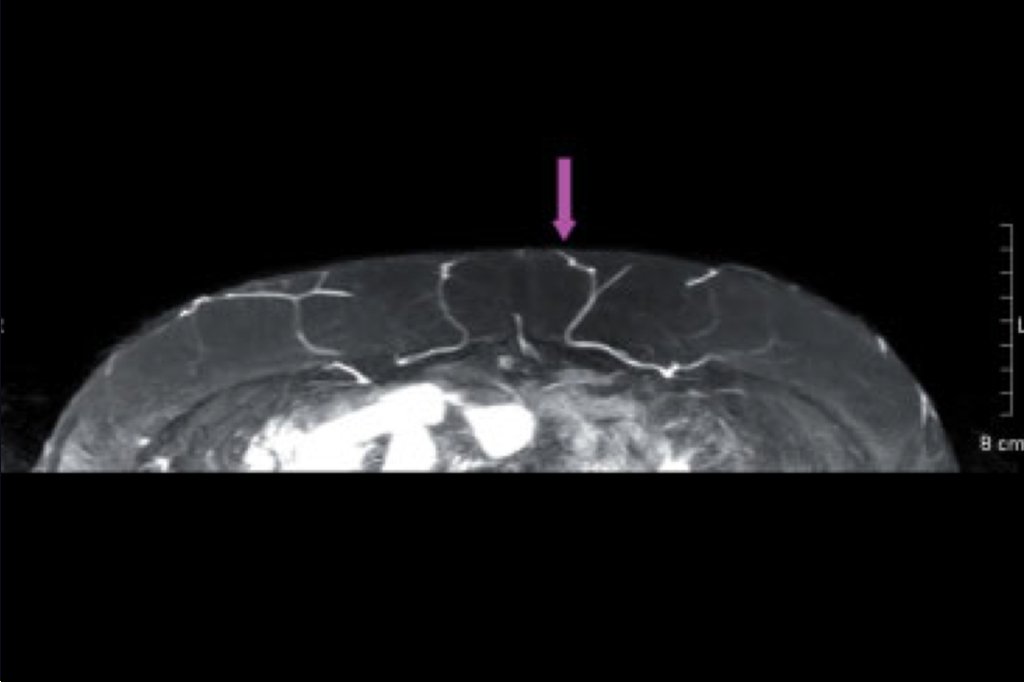

Natural tissue breast reconstruction uses the body’s own natural tissue to reconstruct the breast without the need for implants, which are foreign bodies and as such, will create multiple problems for the patient including the need for future exchange of implants or their removal. Natural tissue breast reconstruction provides a reconstructed breast that feels, looks and behaves like a natural breast. Replacing the skin and soft tissue removed at mastectomy with soft, warm, living tissue is accomplished by borrowing skin and fatty tissue with the blood supply. The most common area fat and skin are taken from (donor site) is the abdomen-DIEP flap. Using sophisticated microsurgical techniques, the underlying muscle is totally preserved. Therefore, the patient does not need to sacrifice a major muscle in her body in order to have a natural, normal looking and feeling breast reconstruction. In addition to reconstructing breast, the contour of the abdomen is often improved much like a tummy tuck. Restoration of the nipple and areola follow. Scars fade substantially with time. Natural tissue breast reconstruction can be used to restore breast after failed or unsatisfactory implant-based breast reconstruction. For many years, Mr Kosutic had dedicated his practice to highly sophisticated forms of microsurgical breast reconstruction called perforator flaps. Most common technique used for natural tissue breast reconstruction called the DIEP flap (Deep Inferior Epigastric Artery Perforator Flap) was developed by dr Robert Allen (USA). Perforator flaps are the state of the art in breast reconstruction. These procedures, otherwise surgically very challenging, have been made safer and more reliable using advanced imaging – CT and MRI scans. Mr Kosutic has published some of the key papers that described these techniques in planning of perforator flap breast reconstruction with the DIEP flap, which have been cited over hundred times in scientific literature and accepted worldwide as the gold standard. Mr Kosutic works with some of the best Consultant Radiologists in North West of England, to capture most important information for planning of these procedures and has developed protocols for CT angiogram and MRI to improve safety and efficacy for every woman in need for breast reconstruction.